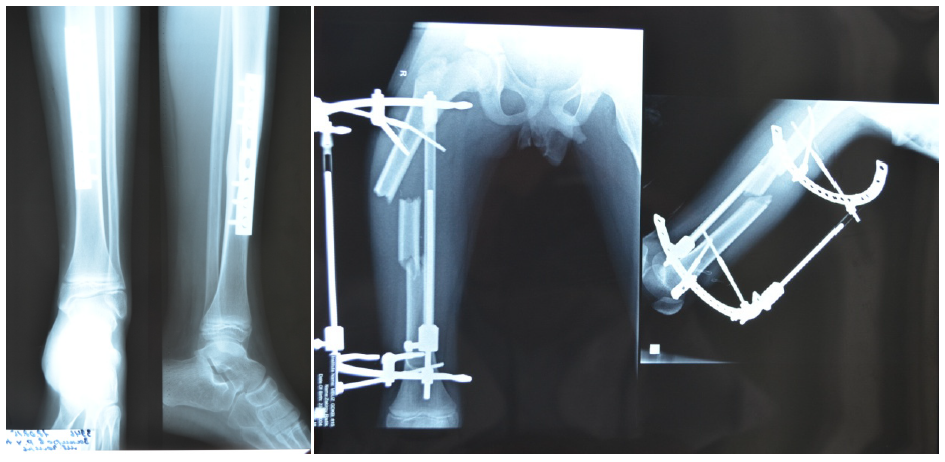

Характер травмы нередко заставлял нас заподозрить гораздо более серьезные повреждения, чем отражают обычные рентгенограммы. Так, под нашим наблюдением был пациент после сочетанной травмы в результате наезда автомобиля в колее в зимнее время, что вызвало раздавливание таза, сопутствующий перелом лучевой кости, черепно-мозговую травму (сотрясение головного мозга). Характер повреждения таза был уточнен через 9 дней после травмы при поступлении больного в клинику с вынужденным положением левого бедра и сильным болевым синдромом (рис. 3).

Больной оперирован на фоне установившейся эутонии. С помощью аппарата Илизарова со стержневой фиксацией было восстановлено тазовое кольцо, одновременно проведено открытое вмешательство с репозицией среднего фрагмента вертлужной впадины, фиксацией спицами (рис. 4).

Пациент достаточно легко перенес предложенную наружную фиксацию, аппарат демонтирован через 5 недель после вмешательства, погружные спицы из таза удалены через 5 месяцев после операции через мини-доступ. Осевая нагрузка начата через 3,5 месяца после травмы.

Рис. 3. Больной К., 13 лет. Травма с раздавливанием таза под колесами автомобиля. Диагноз уточнен при спиральной компьютерной томографии: оскольчатый внутрисуставной перелом вертлужной впадины слева, нарушение переднего тазового кольца

Рис. 4. Больной К., рентгенограммы и внешний вид после оперативного лечения